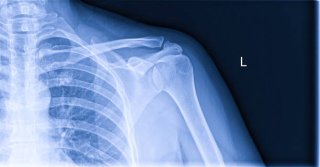

어깨통증 원인 중 통증이 갑자기 심해지는 대표적인 질환이 석회성 건염입니다. 이는 어깨 힘줄에 칼슘이 침착되어 돌처럼 굳는 상태를 말합니다.

석회가 쌓이면 염증 반응이 심해져 갑작스러운 극심한 통증이 발생하며, 팔을 거의 들지 못할 정도가 됩니다.

특징적으로 밤에 통증이 심하고, 자려고 누우면 어깨가 욱신거리거나 찌르는 듯 아픕니다. 엑스레이나 초음파 검사로 쉽게 확인할 수 있으며, 체외충격파나 주사치료로 비교적 잘 치료됩니다.